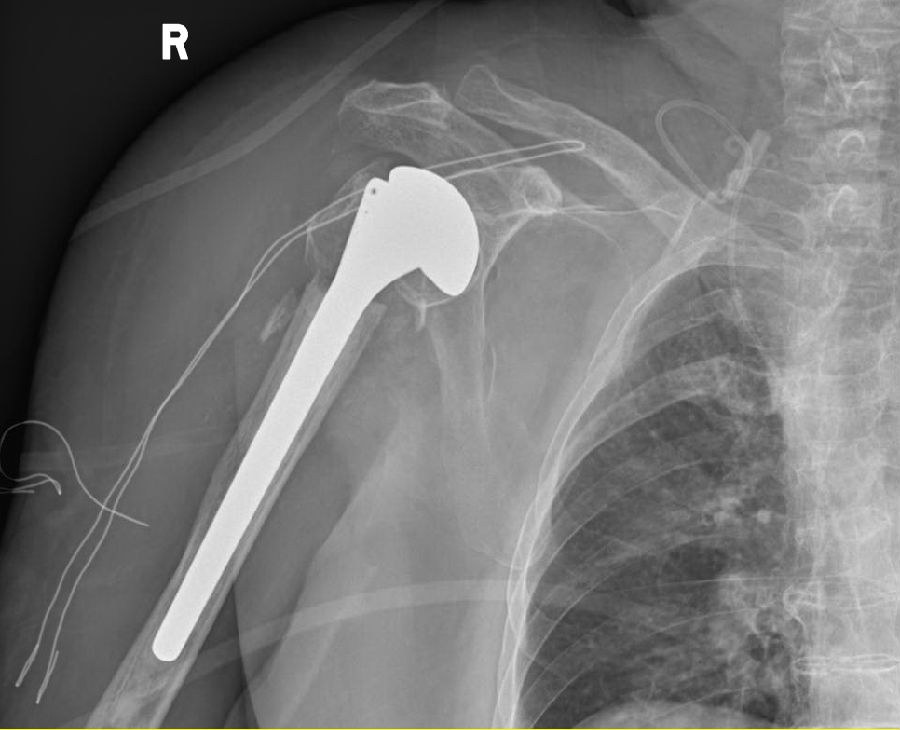

1、行右人工肱骨头置换术(半肩置换),术后影像学检查

综合患者耐受及依从性、骨折类型及粉碎程度、骨量情况、重建后稳定性及康复等因素,决定行右人工肱骨头置换术(半肩置换)及左桡骨远端骨折切复内固定术。